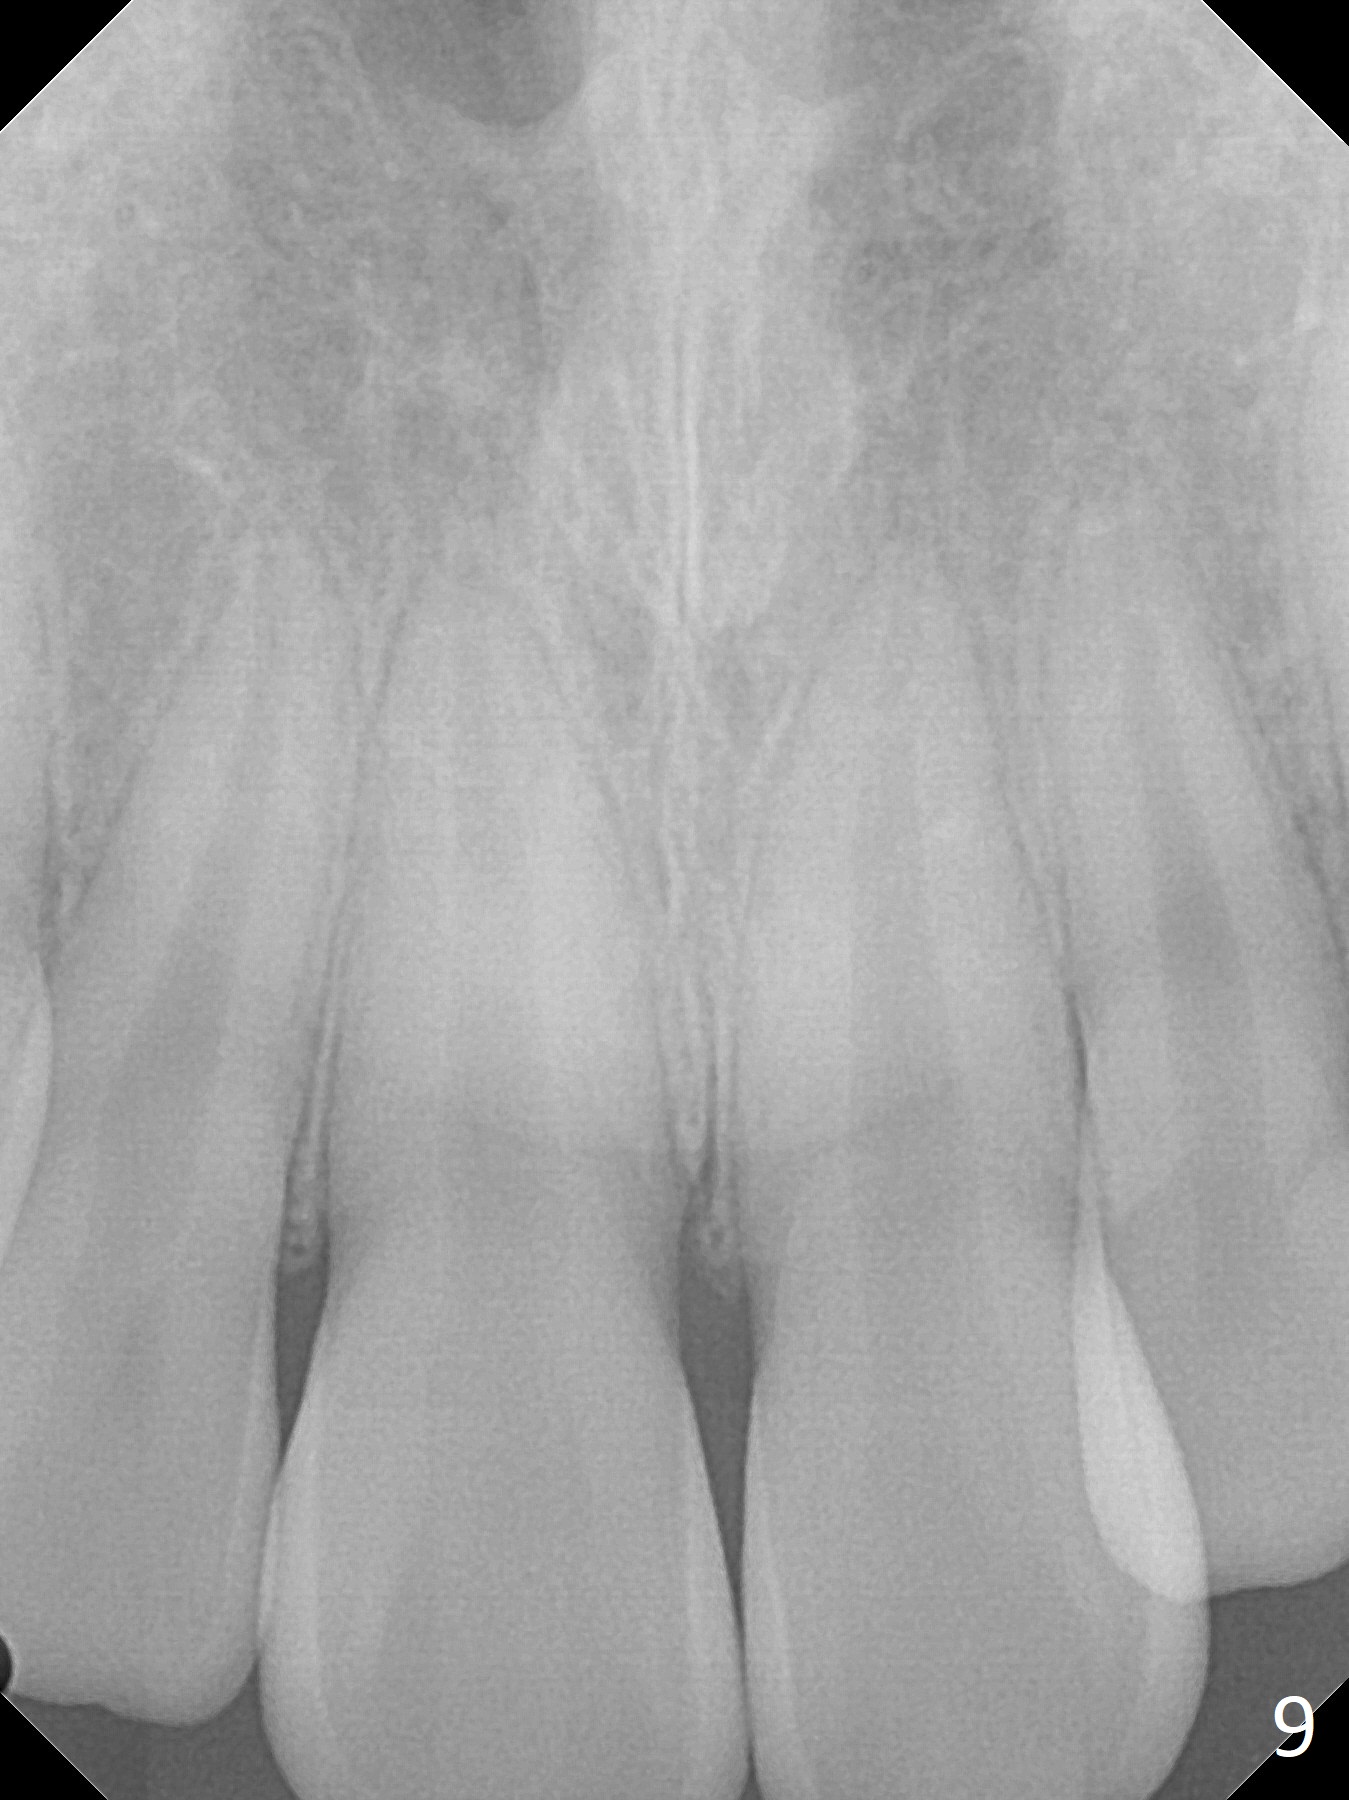

Shallow Overbite

A 12-year-old man has mild lip protrusion (Fig.1,6,7). Orthodontics will be conducted without extraction. Unlike his elder brother, the overbite is shallow. With anterior bracket differential (4-4-5 mm) and mild bimaxillary protrusion, open bite will be created? Or 4-4-4.5mm scheme should be adopted to avoid open bite?